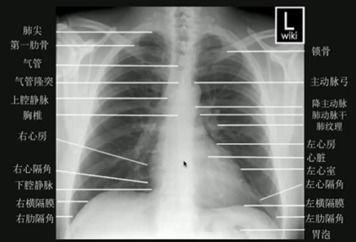

在现代🎯医学的版图中,胸部影像检查(胸片)始终扮演着“前哨兵”的角色。无论是肺部感染、心脏轮廓异常,还是细微的🔥骨骼损伤,胸片都是临床诊断的第一道防线。长期以来,基层医疗机构乃至部分大型医院,都面临着一个难以言说的痛点:影像质量的不稳定性与诊断反馈的滞后性。

“100胸片曝光率”这个概念,在技术层面代表了对X射线曝光控制的极致追求。传统的胸片拍摄,往往受到设备📌老化、操作人员经验差异以及患者体型等多种变量的影响,容易出现“曝光过度”导致细节湮灭,或“曝光不足”导致影像灰暗。这种物理层面上的🔥不确定性,直接增加了漏诊与误诊的风险。

而该软件的核心逻辑,在于利用先进的计算机视觉算法与动态补偿技术,在极短的时间内对原始信号进行数字化重塑。它能够自动识别不同人体组织的密度差异,将曝光率调整至理论上的“黄金点”,确保每一张胸片都能呈现出丝绸般的质感与刀锋般的锐度。

在页游网构建的这个技术生态中,软件的🔥优势并📝非孤立存在。当我们谈论“100胸片曝光率”时,我们谈论的是一种对医学严谨性的致敬。高曝光率带📝来的高清晰度,意味着肺纹理的走向、纵隔的微小位移甚至是早期结节的蛛丝马迹,都能在屏幕上纤毫毕现。这种视觉上的🔥进化,直接降低了放射科医生的阅片难度,将以往需要依靠经验“猜测”的部分,转化为清晰可见的数据证据。